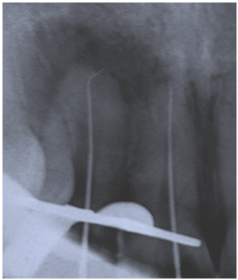

A 24-year-old patient reported to the OPD with a history of trauma 10years ago, which lead to tooth fracture and the tooth was left untreated. The radiograph revealed maxillary lateral with Ellis class III fracture with open apex and apical radiolucency and apexification procedure was planned.

preoperative radiograph

Unlike a regular tooth RCT open apex poses a special challenge while determining the working length. the accuracy of apex locator is less in such cases and a 2D radiograph is not very reliable. A K-file is bent at the tip and manually the apical stop is located and confirmed with a radiograph. This is called Elayouti's technique which improves the accuracy.

Tactile sensation

Shaping and cleaning was done followed by calcium hydroxide dressing for 2 weeks. Later Biodentine was packed in the apical third of the root canal with pluggers and after 12 minutes the Biodentine hardens.

Biodentine placed

later obturation was completed in the rest of the root canal with Guttapercha.

Post operative radiograph